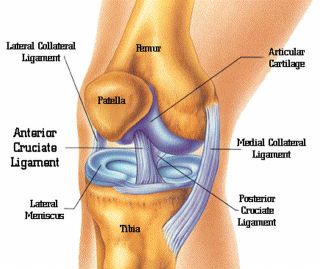

Koljeno

Ozljede meniska koljenog zgloba

Ozljede ligamenata koljenog zgloba

Ostale traume koljena

Sindromi prenaprezanja u području koljenog zgloba

Što je to gonartroza, a što femoropatelarna artroza?

Što je to hondromalacija patele?

Što su to "ikserice", a što "okserice" i koje posljedice nose ti deformiteti?

Što je to osteochondritis dissecans?

Morbus Osgood-Schlatter

Tibia vara (morbus Blount)

Morbus Hoffa

Bolesti koljenih sluznih vreća